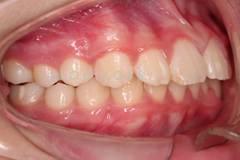

下面這個小患者就存在需早期矯正的問題。通過早期矯正,在不長的時間內(nèi)就達(dá)到極為明顯的療效。她的情況如果等到牙齒替換完畢后再解決,矯治的難度則會非常大。

早期矯正之前